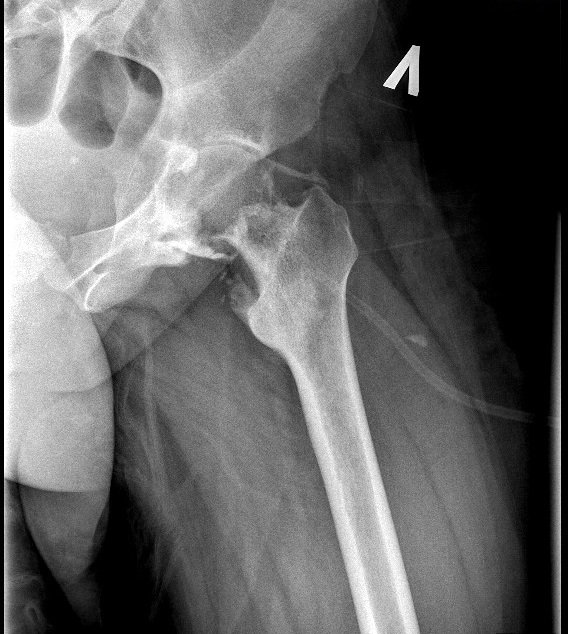

Оссификация тазобедренных суставов: что это и как проявляется?